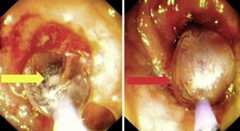

Fig. 3.

Stricture after balloon dilation (green arrow) and area proximal to the stricture (black arrow).